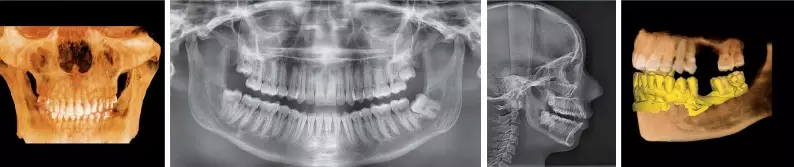

Представляем Green16 — передовую цифровую рентгеновскую систему, объединяющую в себе три ключевые функции: панорамную съёмку, компьютерную томографию (КТ) и сканирование моделей. Этот многофункциональный аппарат разработан для обеспечения превосходного качества изображений при минимально возможной дозе облучения, что стало возможным благодаря инновационным алгоритмам реконструкции и многолетнему опыту компании VATECH в производстве рентгеновского оборудования для стоматологии.

Компьютерный томограф Green16 от VATECH предлагает многослойную панорамную визуализацию Insight Pan, позволяющую исследовать панорамное изображение в глубину. Учитывая индивидуальные различия в форме зубных рядов и наклоне зубов, традиционные панорамные изображения могут упускать важные детали, находящиеся за пределами единственного фокального слоя. Insight Pan решает эту проблему, предоставляя многослойные панорамные изображения, гарантирующие возможность детального изучения всей необходимой анатомии.

Новые инструменты Ez3D-i для моделирования ортодонтического лечения:

• Создание 3D-фото и моделирование эстетических изменений

• Модуль Ortho позволяет моделировать перемещение зубов и челюстных костей на основе данных 3D-реконструкции и 3D-сегментирования. Каждое перемещение протоколируется и может быть сохранено как отдельный план лечения.

• Моделирование дистального перемещения нижней челюсти и перемещения отдельных зубов.

• Планирование ортогнатической хирургии с возможностью прогнозирования изменений мягких тканей лица на основе 3D-реконструкции и 3D-фотографии.

• Автоматическая сегментация зубов и костей с возможностью экспорта данных в формате STL.

• Функция виртуального удаления зубов для планирования ортодонтического лечения без удаления зубов, а также для планирования имплантации.